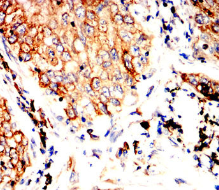

BCL6 Mouse Monoclonal antibody[7A6D1]

IHC    1/200 - 1/1000